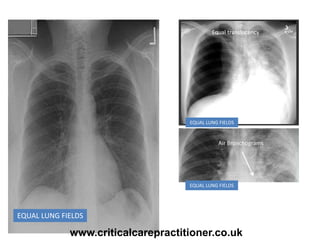

EQUAL LUNG FIELDS

Equal translucency

Air Bronchograms